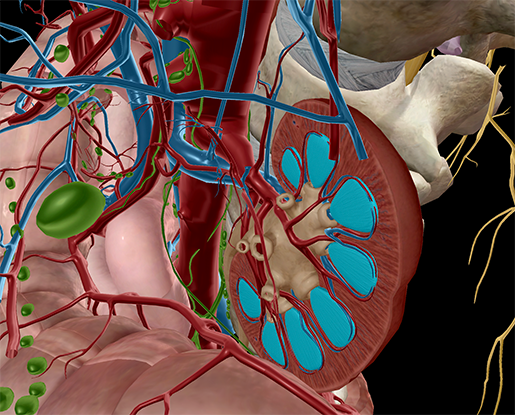

The kidneys are 11 centimeters long paired reddish brown organs situated on the posterior wall of the abdominal cavity one on each side of the vertebral column and capped by the adrenal gland. H ions are produced as a natural byproduct of the metabolism of dietary proteins and accumulate in the blood over time. Connective tissue anchors the kidneys to surrounding structures and helps maintain their normal position.

Upper portions of the kidneys are somewhat protected by the eleventh and twelfth ribs figure 1. Anatomy of the kidneys. Each kidney weighs about 125175 g in males and 115155 g in females.

Due to the presence of the liver the right kidney is slightly lower than the left kidney. They are about 1114 cm in length 6 cm wide and 4 cm thick and are directly covered by a fibrous capsule composed of dense. Anatomy of the urinary system.

The kidneys monitor and regulate the levels of hydrogen ions h and bicarbonate ions in the blood to control blood ph. Glomerular filtration glomerular filtration is the renal process whereby fluid in the blood is filtered across the capillaries of the glomerulus. The right kidney is lower than the left due to displacement by the liver.

Location of the kidneys there are two kidneys which lie retroperioneally in the lumbar area. The angiotensinconverting enzyme converts angiotensin i to angiotensin ii which stimulates the adrenal cortex to secrete aldosterone a hormone that is involved in increasing blood pressure. The basic anatomy and physiology of the kidney how kidney function changes through life the anatomy of the kidney the kidneys are comple x and beautiful organs.